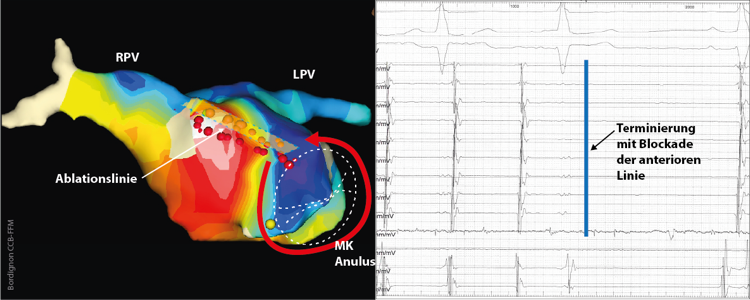

atyp-vorhofflattern

(Abb. 3) Elektroanatomische Rekonstruktion eines linken Vorhofs und Darstellung eines farbkodierten Aktivierungsmaps. Die früheste Erregung liegt septal, die späteste unmittelbar kranial davon („Early meets late“), der Reentry läuft perimitral im Gegenuhrzeigersinn. Durch Ablation einer Läsion zwischen MK Anulus und rechter oberer Pulmonalvene (RPV) terminiert die Tachykardie.